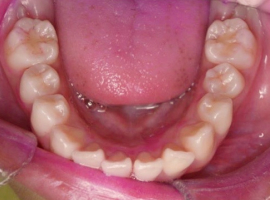

下顎

- After